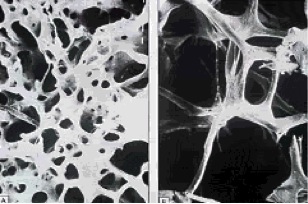

osteoporosis

Published November 17, 2013 at 308 × 204 in Wrist Fracture